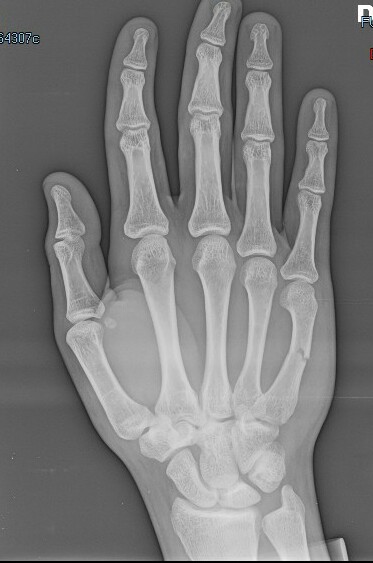

Salve sono un ragazzo di 17 anni che ha subito una forte contusione provocando una frattura composta del V metacarpo della mano dx. Recandomi in pronto soccorso mi hanno fatto un rx e ingessato bloccando mignolo e anulare per 30 giorni.. siccome sono già 8 giorni che porto il gesso ( premetto che mi sono recato in ps dopo 7 giorni, pensando fosse una contusione) la mia domanda è, guardando il tipo di frattura, siccome non sopporto il gesso per il caldo è per i fastidi che provoca.... Posso già toglierlo? La frattura di consoliderà lo stesso? Cosa potrebbe succedere?

Commento file: Rx dopo 7 giorni